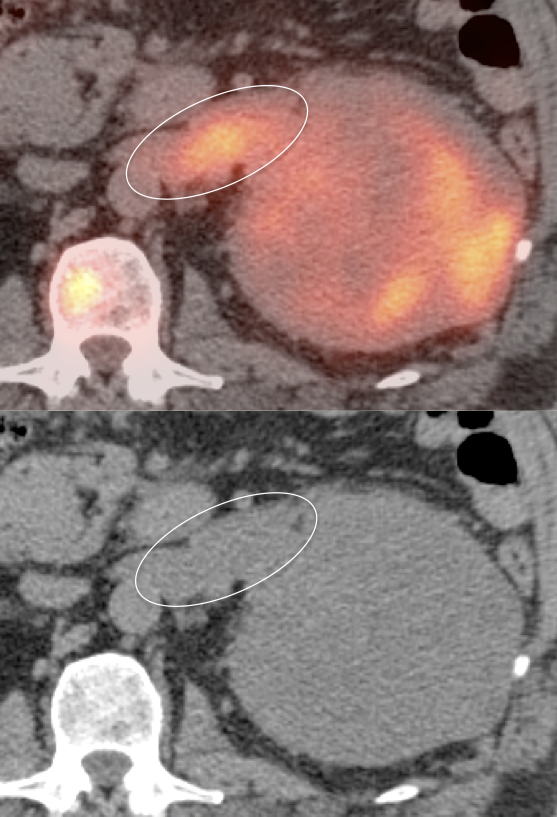

1. FDG is excreted and accumulates in the kidney, easily masking areas of pathologic uptake.

2. Many renal cell carcinomas are only mildly FDG-avid.

3. Nearly every PET/CT scan is performed without intravenous contrast, markedly limiting evaluation of the kidneys on the CT portion of the exam.

• These 3 limitations lead to a sensitivity of only ≈ 60% for the detection of a primary RCCA lesion.

Primary Lesion:  Because many primary RCCA lesions are only mildly FDG avid, we must raise a suspicion of RCCA for any FDG-avid renal lesion (cystic or solid) — unless we can clearly characterize it as a fat-containing angiomyelolipoma.

Metastatic Disease: Metastatic RCCA lesions are usually more FDG avid than the primary lesion (nearly all demonstrate metabolic activity greater than liver uptake).

• Lesion masked by normal urine activity